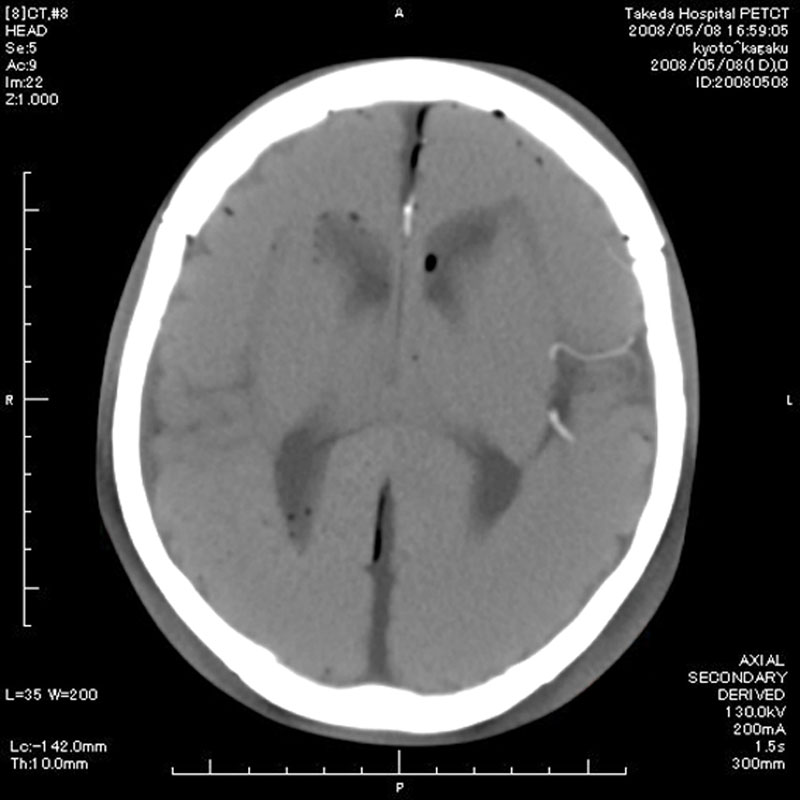

- Dieses Modell besteht aus einem synthetischen Schädel, welcher in einen Kunststoffkopf eingegossen ist.

- In der linken Schädelhälfte sind die vordere und mittlere Hirnarterie nachgebildet und mit Kontrastmittel gefüllt.

- Der Durchmesser der simulierten Arterien reicht von 0,5 mm bis 4 mm.